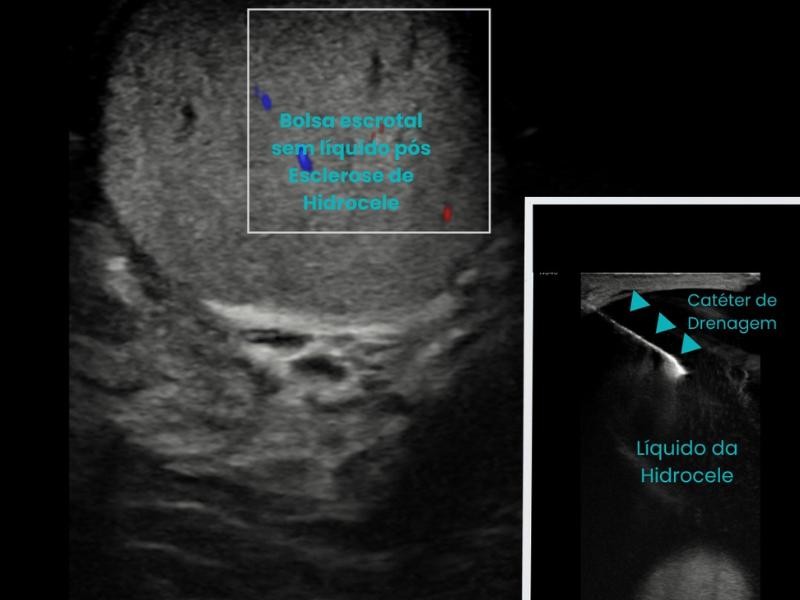

A Esclerose de Cisto consiste na drenagem do líquido contido na lesão, seguida da introdução de um agente esclerosante para evitar a recidiva do cisto. O procedimento é realizado com precisão através de imagem em tempo real, como ultrassonografia ou tomografia, garantindo segurança e eficiência.

Primeiramente o paciente recebe pomada anestésica e anestesia local para evitar qualquer incomodo. O procedimento é realizado com auxílio de ultrassom ou tomografia para guiar a introdução de uma agulha dentro do cisto. O líquido é aspirado, e em seguida, um agente esclerosante, como álcool absoluto e polidocanol, é injetado para obliterar a cavidade e impedir sua recidiva.